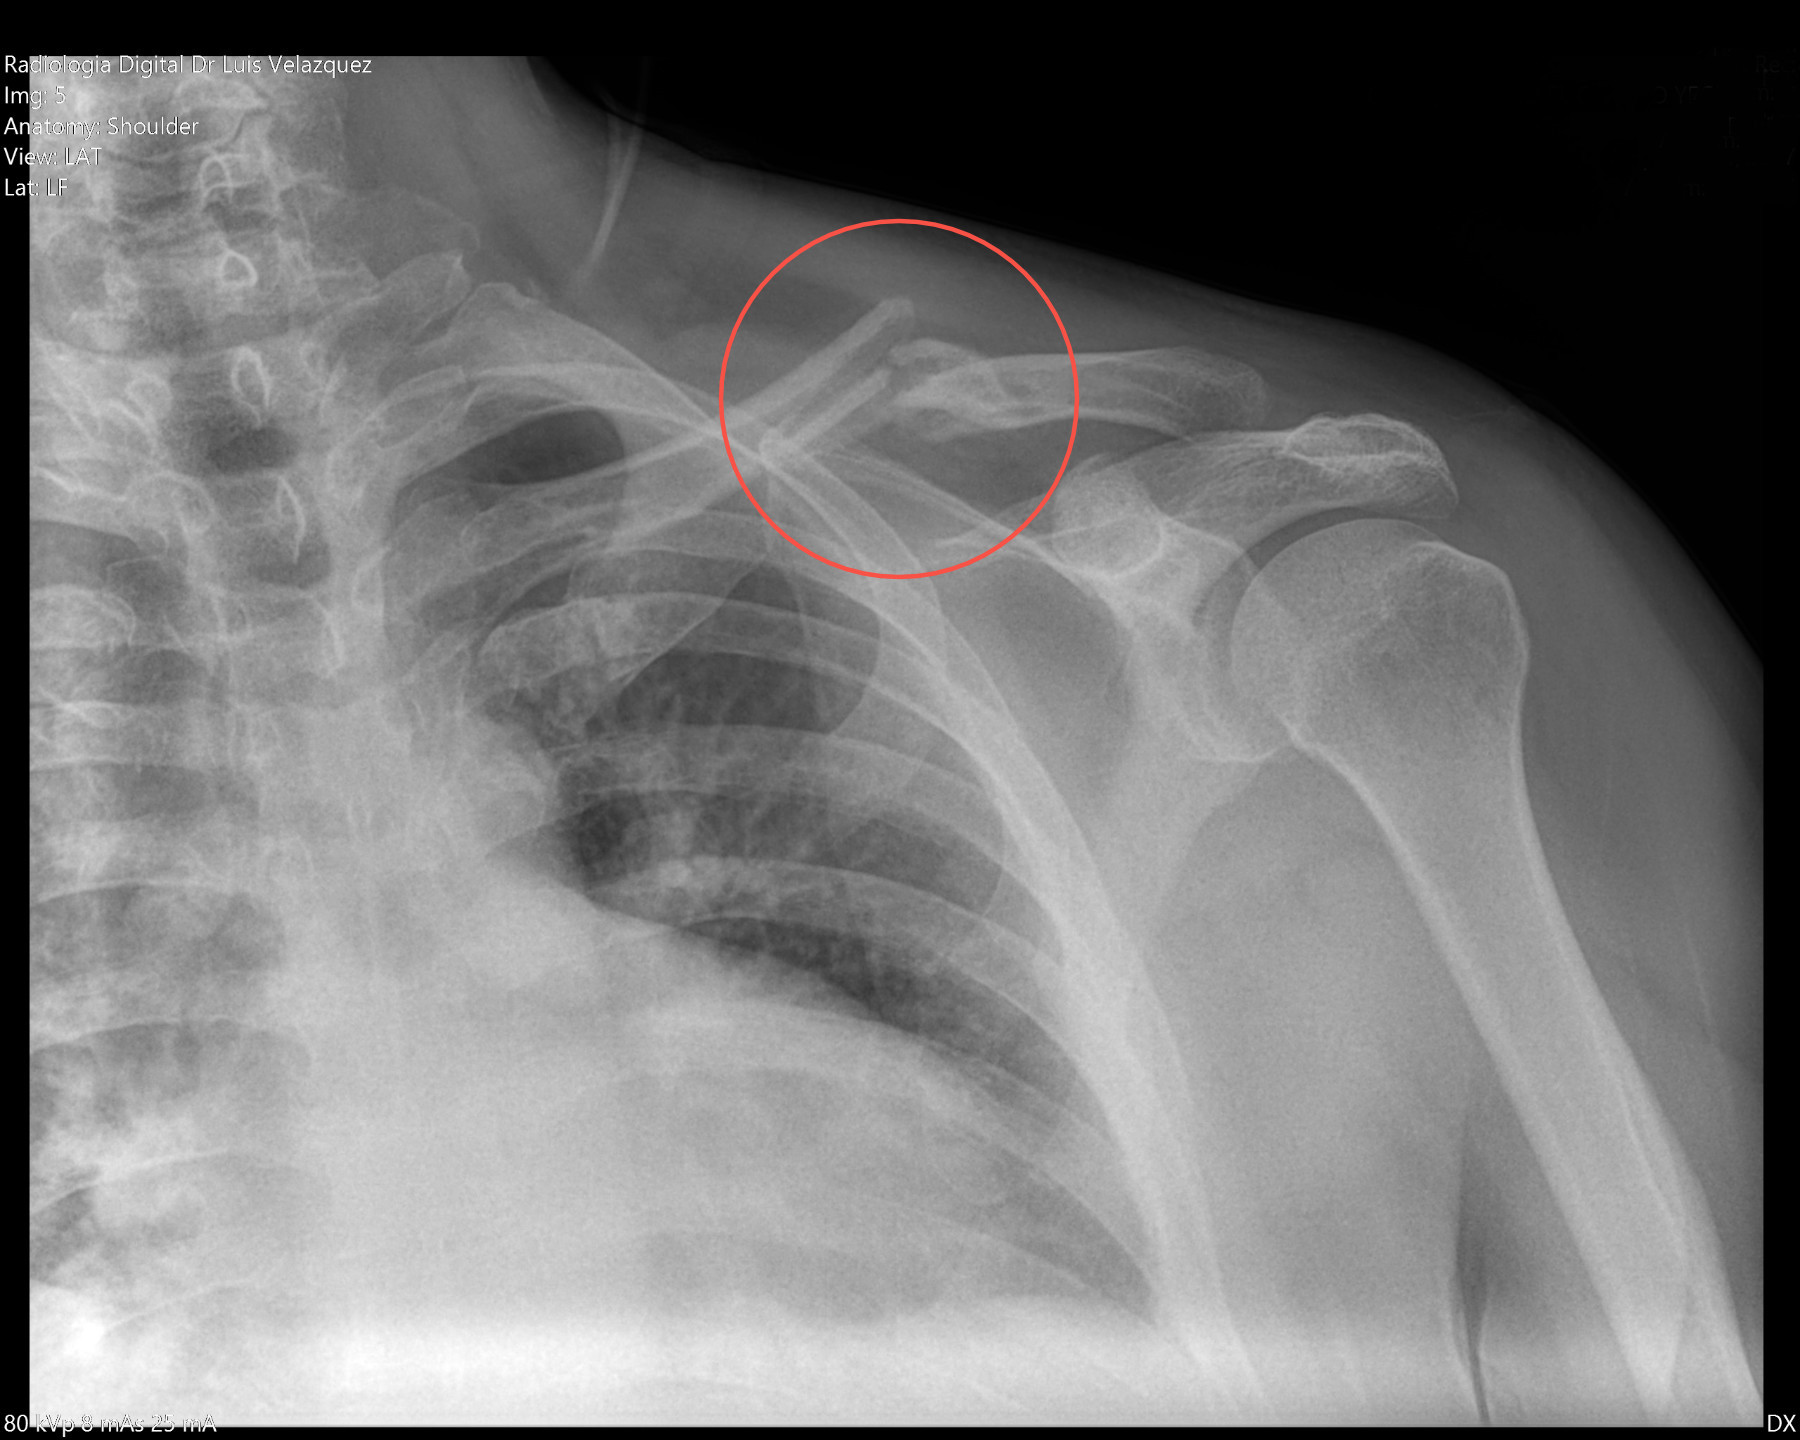

Radiología Digital como Herramienta Complementaria en el Dictamen de Bienes Muebles